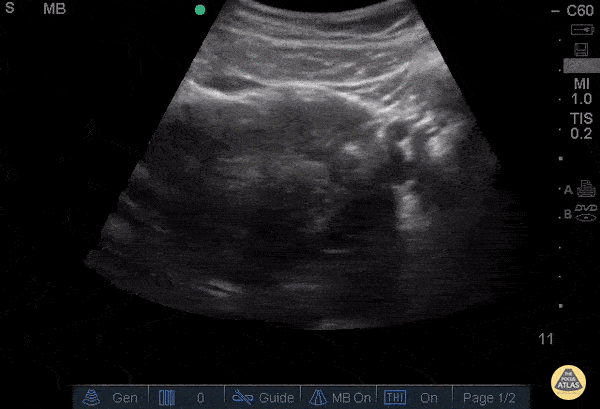

29 y/o female with intermittent lower abdominal and vaginal pain and nausea x3 days. LMP 3.5 weeks prior. Transabdominal ultrasound demonstrates pregnancy in cornu of the uterus. Symptoms progressed over 24 hours and patient became hypotensive and was taken to OR for exploratory laparotomy and found to have ruptured cornual ectopic with hemoperitoneum. Stacey Frisch, MD Juliana Jaramillo, MD Stephan Rinnert, MD - Kings County/SUNY Downstate Emergency Medicine